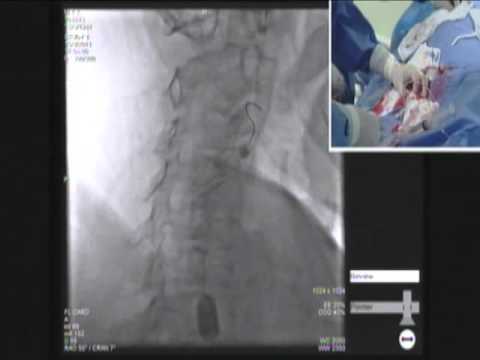

Carotid artery Stenting With Distal Emboshield filter ...

Occluded Internal Carotid Artery Reopened Using Carotid Stent with Distal Protection Device and MERC - Duration: 3:15. Michael Horowitz 1,241 views ... View Video